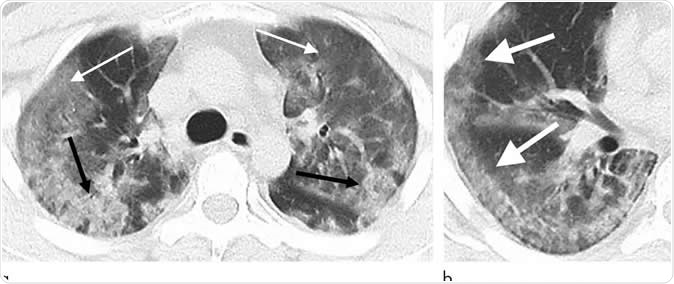

29-year old male with unknown exposure history, presenting with fever and cough, ultimately requiring intensive care unit admission. (a) Axial thin-section non-contrast CT scan shows diffuse bilateral confluent and patchy ground-glass (solid arrows) and consolidative (dashed arrows) pulmonary opacities. (b) The disease in the right middle and lower lobes has a striking peripheral distribution (arrow). Image Credit: Radiological Society of North America

CT scan images of these patients’ chests revealed certain common features including, ground glass opacities and consolidation features over the lungs. The team also noted the number of lobes of the lungs that were affected with ground glass opacities and consolidation and the degree of involvement of each of these lobes of the lungs. Based on these the team also looked at the overall total severity scores. They also noted absence of nodules in the lungs and fluid in the pleural cavity (pleural effusion). There was involvement of some of the lymph nodes of the thorax and these were abnormal in size and shape, they wrote. Some of the patients also had underlying lung diseases such as fibrosis and emphysema. These features were all recorded for the patients with the coronavirus infections. The team found some additional features such as crazy paving patterns and distribution of the changes in the peripheral parts of the lungs. There may be absence of cavity formation within the lungs along with some clear-cut nodules, they wrote.  Pleural effusions and lymphadenopathy may also be absent they wrote.

Among seven of the eight patients, there was a slow progression of the lung disease with rising areas of airspace opacities, they wrote. The team wrote in their study, “Typical CT findings included bilateral pulmonary parenchymal ground-glass and consolidative pulmonary opacities, sometimes with a rounded morphology and a peripheral lung distribution.”